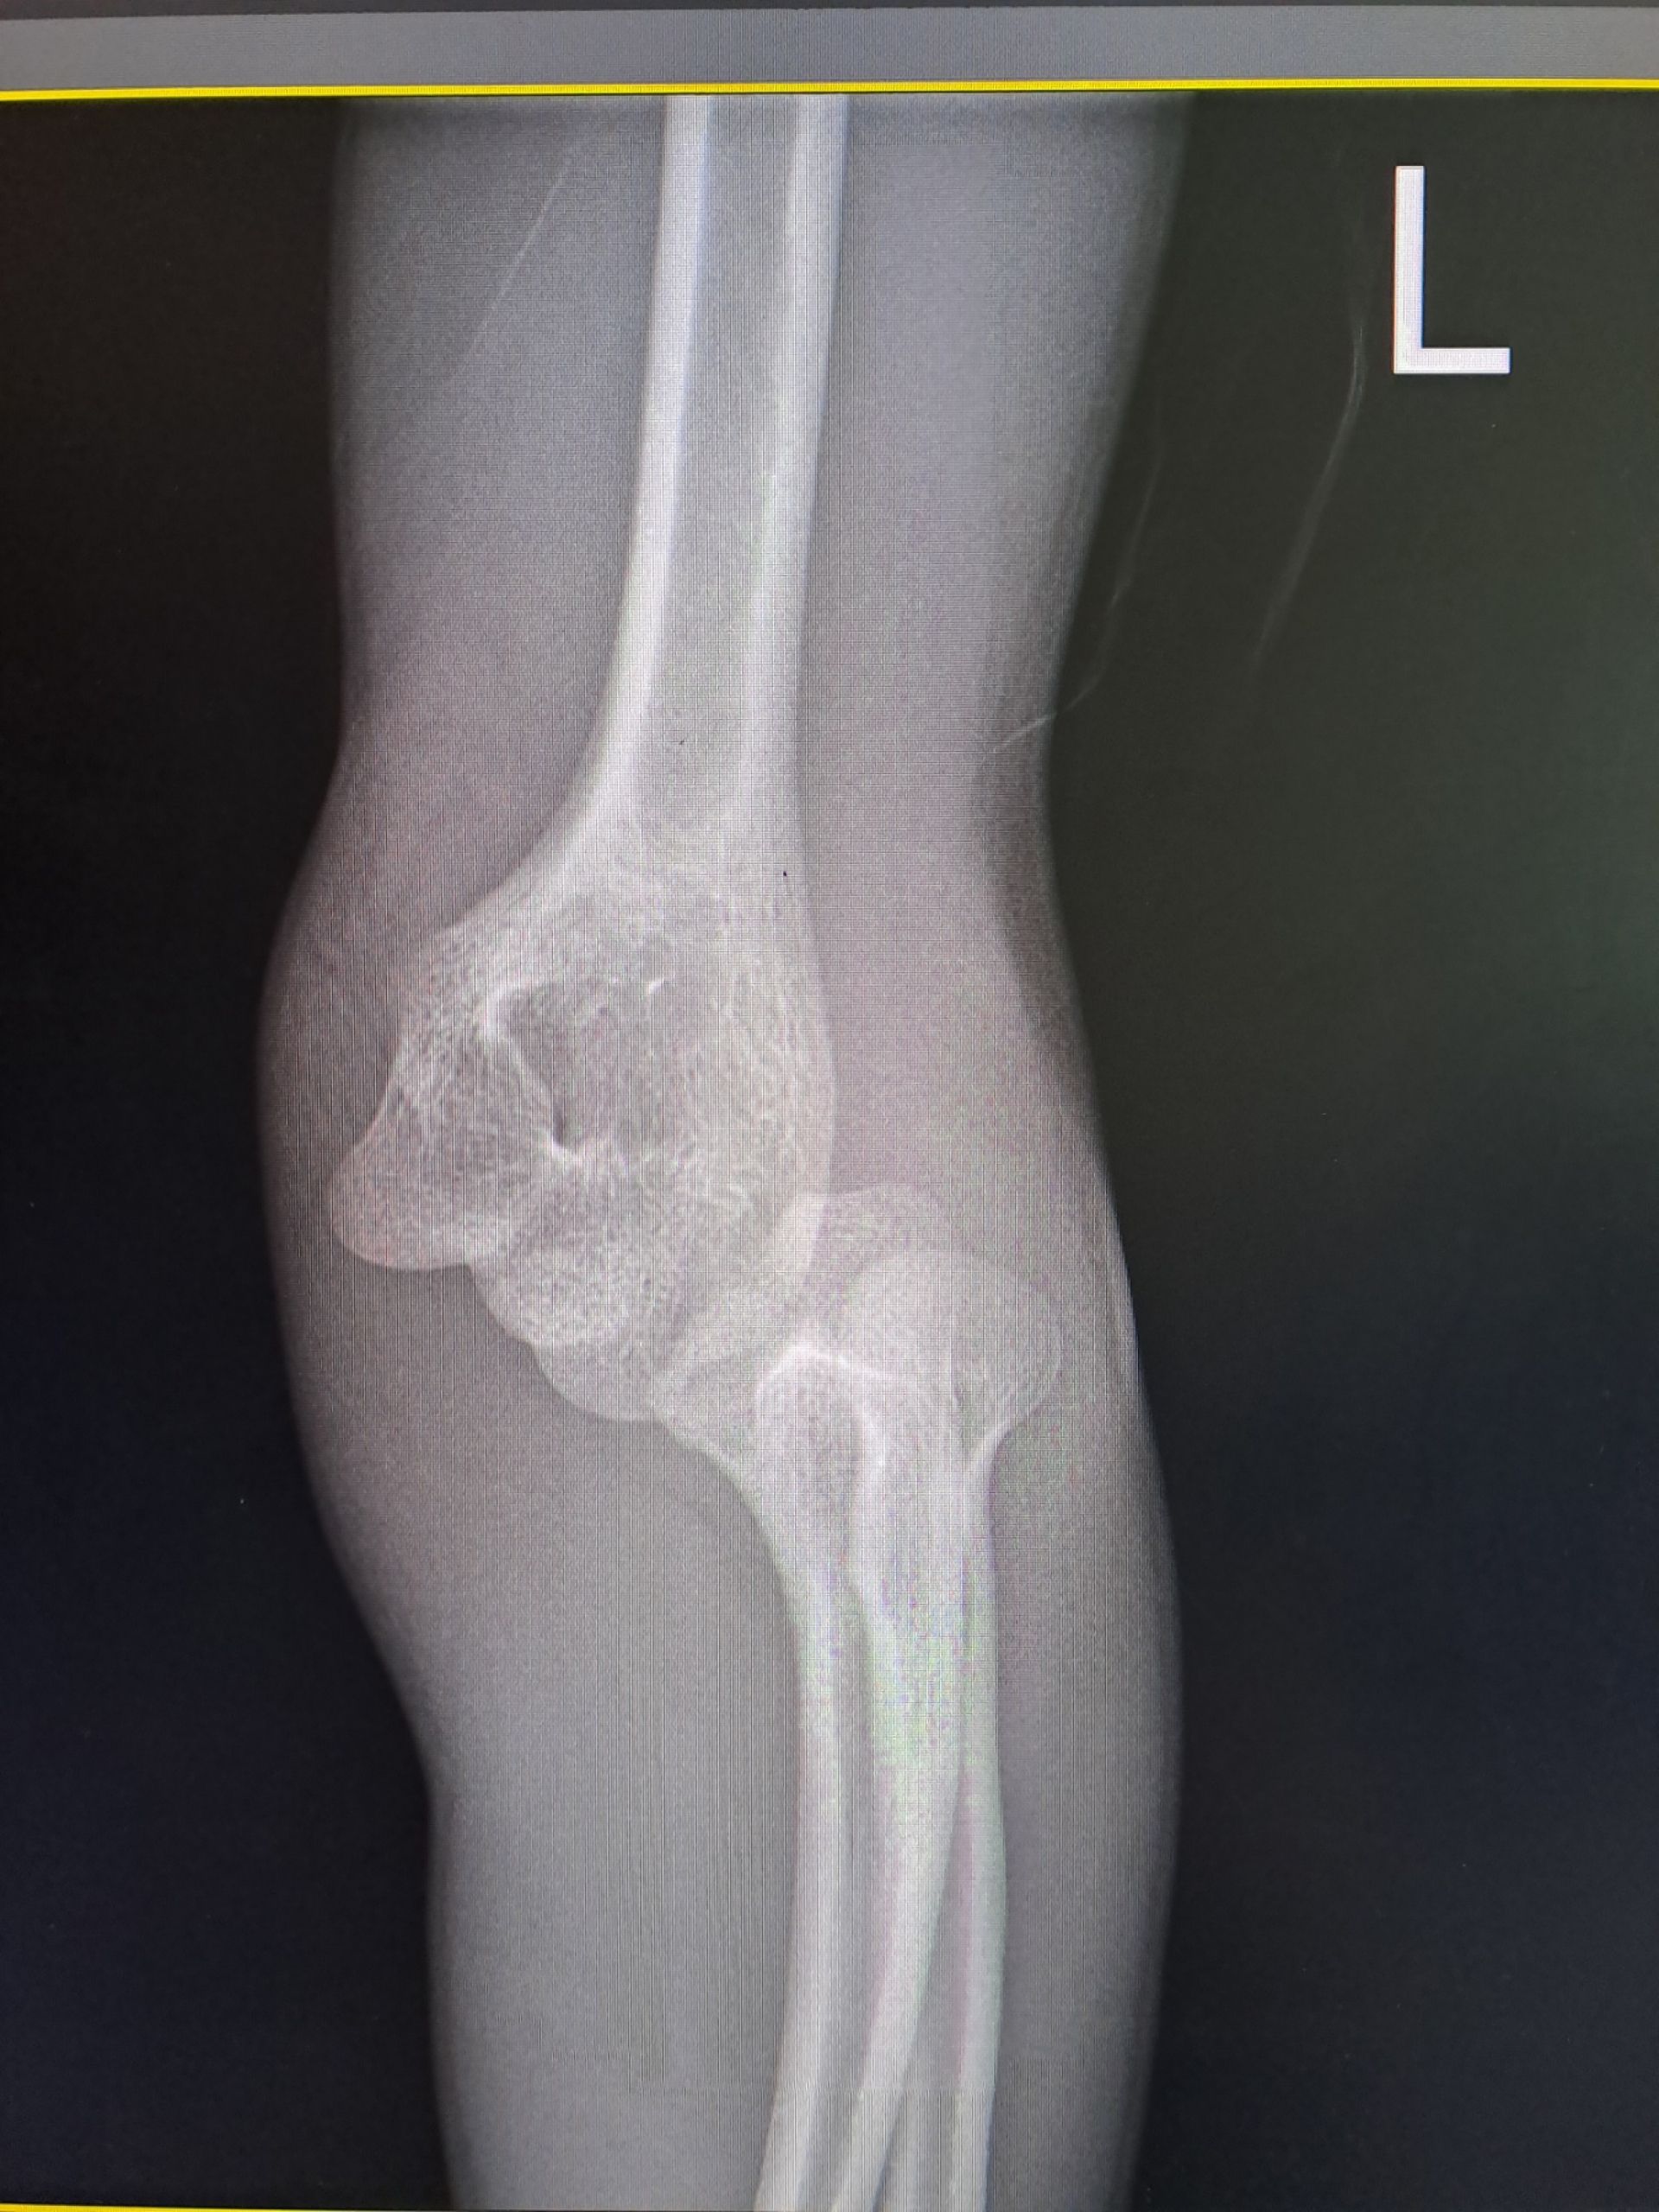

Хлопчик потрапив до травмпункту з вираженим болем та сильною деформацією ліктя. Рентген підтвердив найгірші побоювання медиків: закритий вивих передпліччя разом із переломом плечової кістки. Таке ушкодження вважається нестабільним — це означає, що суглоб буквально «розійшовся», а зв’язки та капсула зазнали значних розривів, передає Вінницька обласна дитяча клінічна лікарня.

Сьогодні цей складний шлях уже позаду. Лікарі провели планове видалення металевих фіксаторів і констатували: функція ліктя відновлена на 100%. Хлопчик не відчуває болю, не має обмежень у рухах і вже повернувся до своєї звичної фізичної активності.